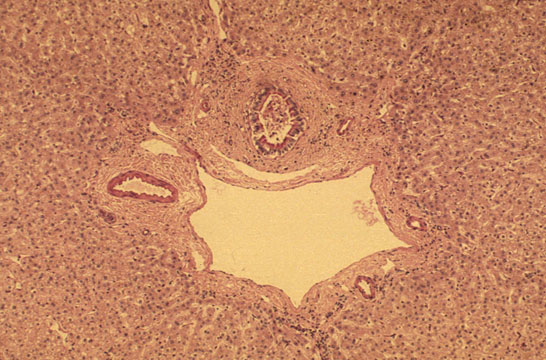

Formations of the Septal Space

Septal Space

Fig 25 - LARGER SEPTAL SPACES: contain larger vessels and bile ducts.Concentric fibrosis around bile ducts in these spaces is normal and should not be interpreted as a pathological change.

CONTENTS